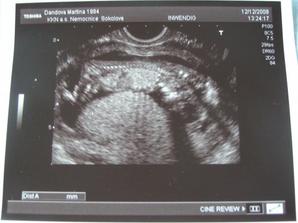

Tak od 12. do 15.12. jsme byli v nemocnici na pozorování, mimísek nás trošku pozlobil a postrašil. Teď už je ale vše v pořádku, bylo to jen nerové, maminka prožila neradostnou zprávu a odrazilo se to na nás ☹ Ale snad už jsme to zvládli a nebude se to opakovat. Miminko se vyvíjí tak jak má a srdíčko tluče o 106 🙂///////